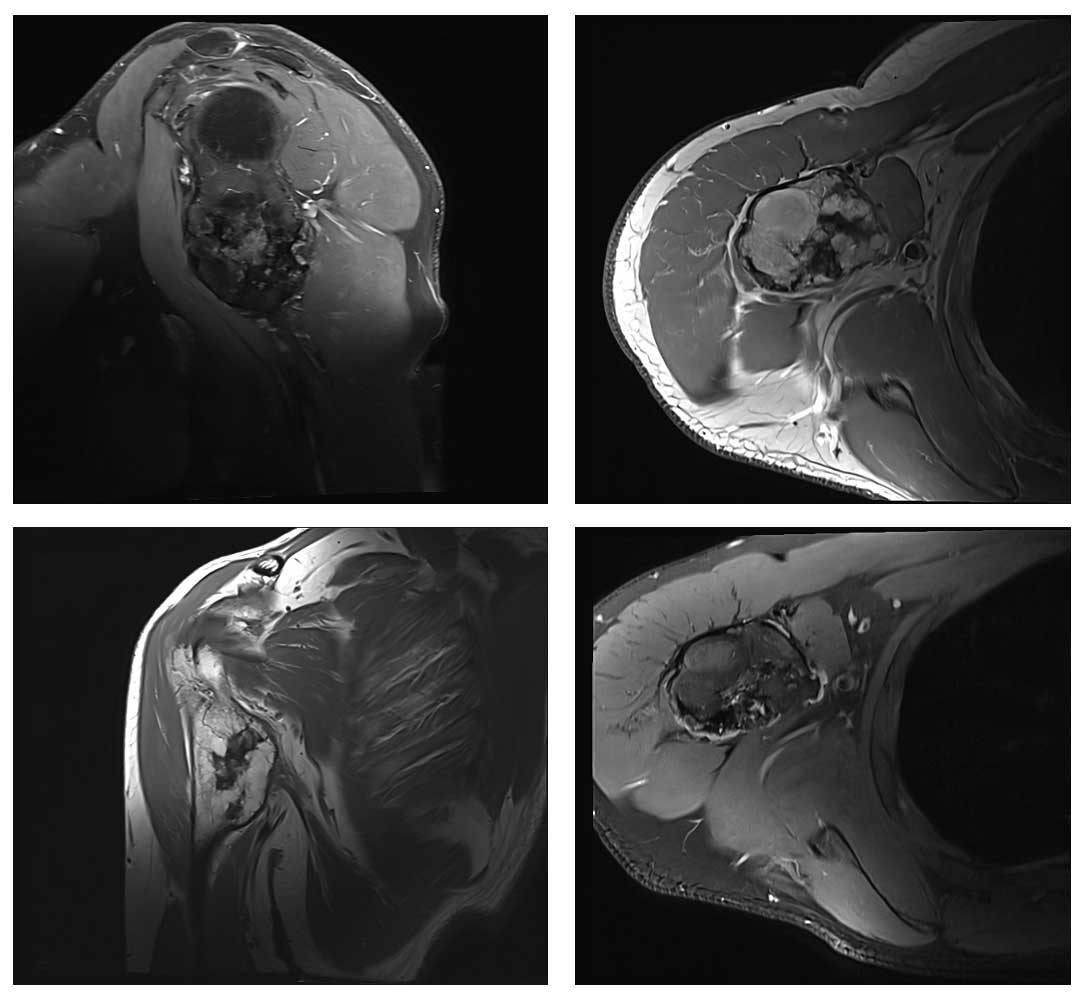

Ameliyat Öncesi: MR’da kitlenin vasküler yapılara yakınlığı görülmekte.